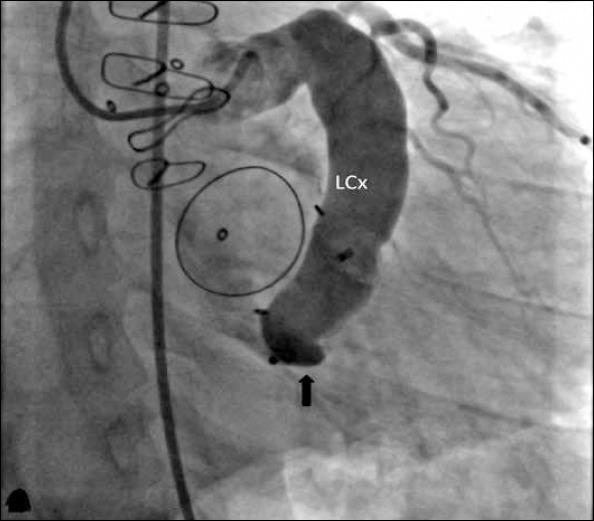

Göksülük Hüseyin, Alpman Ahmet, Atmaca Yusuf, Gerede Menekşe, Özcan Özgür Ulaş, Erol Çetin

Department of Cardiology, Faculty of Medicine, Ankara University; Ankara-Turkey.

Anatol J Cardiol. 2015 May 22;15(6):E17-8. doi: 10.5152/akd.2015.6318.